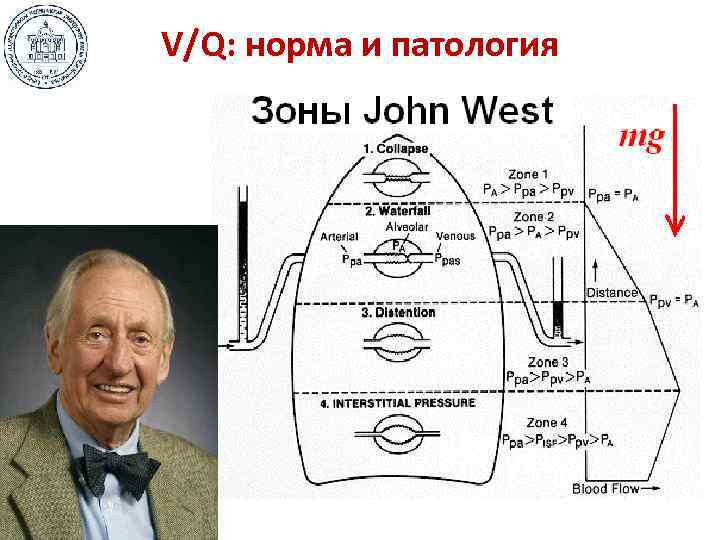

РIP 20 см, РЕЕР 10 см, F 12 мин-1, I: E 2: 1, FIO 2 1, 0

РIP 20 см, РЕЕР 10 см, F 12 мин-1, I: E 2: 1, FIO 2 1, 0

Puritan-Bennett 740 VCV: VT 300 мл, F 14 мин-1, РЕЕР 10 см Respironix Esprit PCV: PIP 20 см, F 10 мин-1, РЕЕР 10 см, I: E 2: 1

Puritan-Bennett 740 VCV: VT 300 мл, F 14 мин-1, РЕЕР 10 см Respironix Esprit PCV: PIP 20 см, F 10 мин-1, РЕЕР 10 см, I: E 2: 1